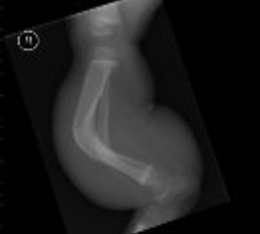

X-rays show a severe tibial deformity corrected with a Taylor Spatial frame.